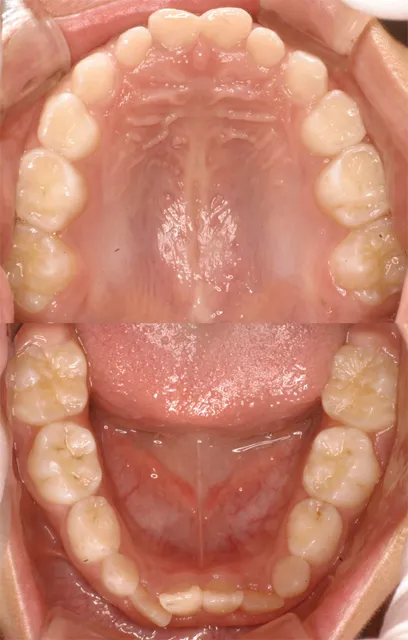

ご説明:説明は口腔写真とレントゲンを対比して、2つのモニタで表示した画面を見ながら行います。 また、口腔写真やレントゲン写真は 、画像を印刷してファイリングしてからお渡しするサービスを行っています。